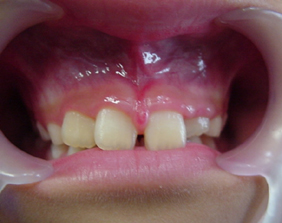

術前口腔内写真

上唇の小帯(ヒダ)が長すぎて正中離開になっています。